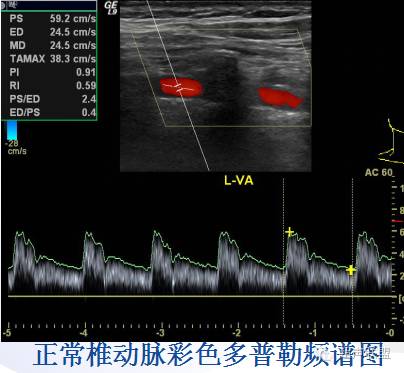

椎动脉VA | 0.3—0.4 | 0.52±0.14 | 0.62±0.05 | 颈椎横突孔 |

7、评价椎动脉VA血流:颈总动脉长轴切面向外平移1-2cm,在椎间隙间断显示VA长轴,测量VA内径、记录典型VA血流频谱及CDFI血流图,注意VA有无反流与狭窄。